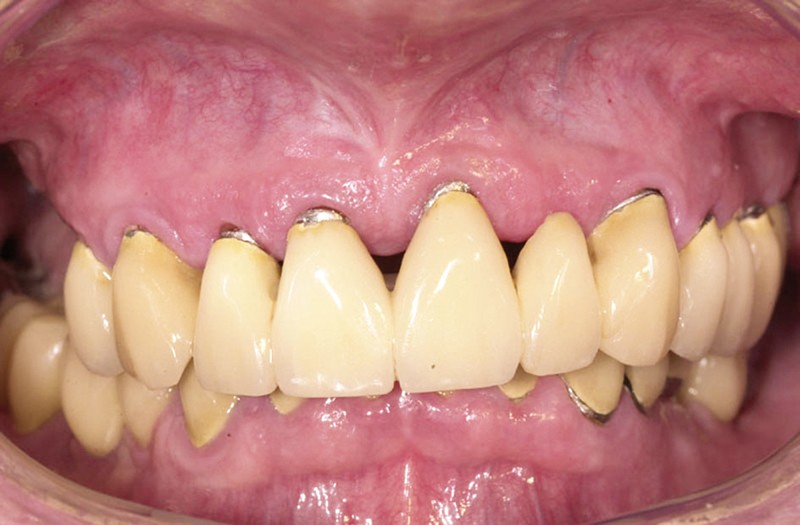

À la pose de la couronne implantaire, on notait une parfaite intégration des tissus mous(fig. 1a et b).

Lors de la maintenance de 2016, le contrôle de plaque de la patiente est toujours excellent et les tissus implantaires ne présentent pas de signes inflammatoires(fig. 2a et b).